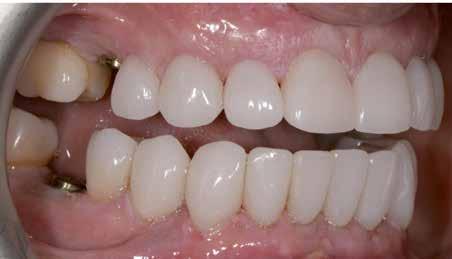

KOMPLEX FOGAZATI REHABILITÁCIÓ

A fogazat „megfiatalítása” láthatatlan fogszabályzó készülékek

segítségével

A fogazat elhasználódása alatt azoknak a degeneratív folyamatoknak az összesített hatását értjük, melyeken az élet során a szervezet keresztülmegy. Ezek lehetnek a fogérintkezések közben fellépő mechanikai erők (abrázió, attríció), endogén vagy exogén eredetű savas közegek által kiváltott kémiai behatások (erózió), kariogén baktériumok által okozott pathológiás folyamatok és parodontális elváltozások, valamint iatrogén ártalmak.

A felnőtt páciensek kezelése során általában egyszerre több ellátásra szoruló elváltozást is diagnosztizálhatunk: hiányzó fogak, kopott fogazat, esetleg régi, nem megfelelő, sérült fogpótlások, rendellenes helyzetben lévő fogak stb… Ezen páciensek kezelésekkel kapcsolatos kérései mindig az esztétikai vagy a rágással kapcsolatos kívánságaik kielégítését szolgálja. A kezelések során a fogorvosoknak nem csak a páciensek kéréseinek teljesítésére, hanem ezzel egyidejűleg a fogazat általános megjelenésének és funkciójának lehetőség szerinti javítására is törekedniük kell. Mindemellett a lehető legtöbb saját foganyag megőrzését és az évek során elvesztett kemény- és lágyrészek pótlását (pl.: hiányzó fogak, sorvadt állcsontgerinc, lágyszöveti defektusok) is szem előtt kell tartaniuk, úgy, hogy közben egy hosszú távon fenntartható eredményekkel járó kezelési tervet állítanak össze. Ezek mindig összetett esetek. Annak érdekében, hogy a fentiekben megfogalmazott összes kezelési célt teljesíteni tudjuk, interdiszciplináris megközelítésre van szükség. Az ilyen komplex rehabilitációs kezeléseket „fogászati megfiatalításnak” nevezzük. Ezeknek a beavatkozásoknak lényege az elhasználódott fogazat biológiai szempontokat figyelembe vevő minimál invazív módon történő helyreállításában rejlik, mely folyamat végére a páciensek fogai visszanyerhetik fiatalkori megjelenésüket.

A rehabilitációs kezeléseknek a célja, hogy a páciensek a lehető leghosszabb időn keresztül képesek legyenek mosolyogni és rágni. A protetikai kezeléseket végző fogorvosoknak helyre kell tudni állítaniuk a fogívek szabályos lefutását és az alsó és felső fogív között megfelelő interokkluzális érintkezéseket kell létrehozniuk. Így lehet csak az ellátás befejezését követően elért végeredmény biológiai szempontokat figyelembe vevő esztétikáját, funkcionális megfelelőségét, hosszú távú fenntarthatóságát biztosítani.